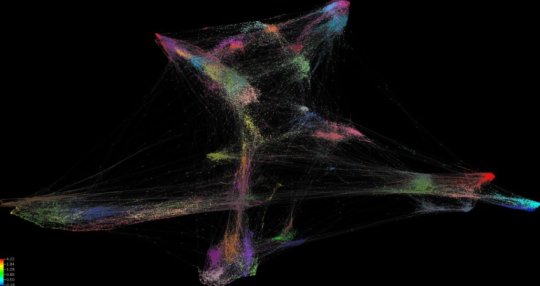

In a paper recently published and featuring on the cover of the Journal of Immunology, the scientists have shown the incredible diversity of immune cells that are inside a colorectal tumour. Immune cells are known to protect against cancer growth and this work provides new information on the types of cells present and how they might be beneficial for the patient.

Lead researcher Associate Professor Roslyn Kemp explains they are using a new technology called high dimensional mass cytometry to identify cells in the tumours of people with bowel cancer.

“It can be thought of as taking a higher resolution ‘photo’ of the inside of the tumour. The photo may reveal new types of cells that may or may not be targetable by drugs, or reveal different composition of immune cell populations in individuals that could be used to predict the course of the disease.”

Associate Professor Kemp says results of their study have shown there is huge diversity in the type of immune cells that infiltrate the tumour, which means that any one, or more likely a combination of many immune cells, could have an effect on patient outcomes.